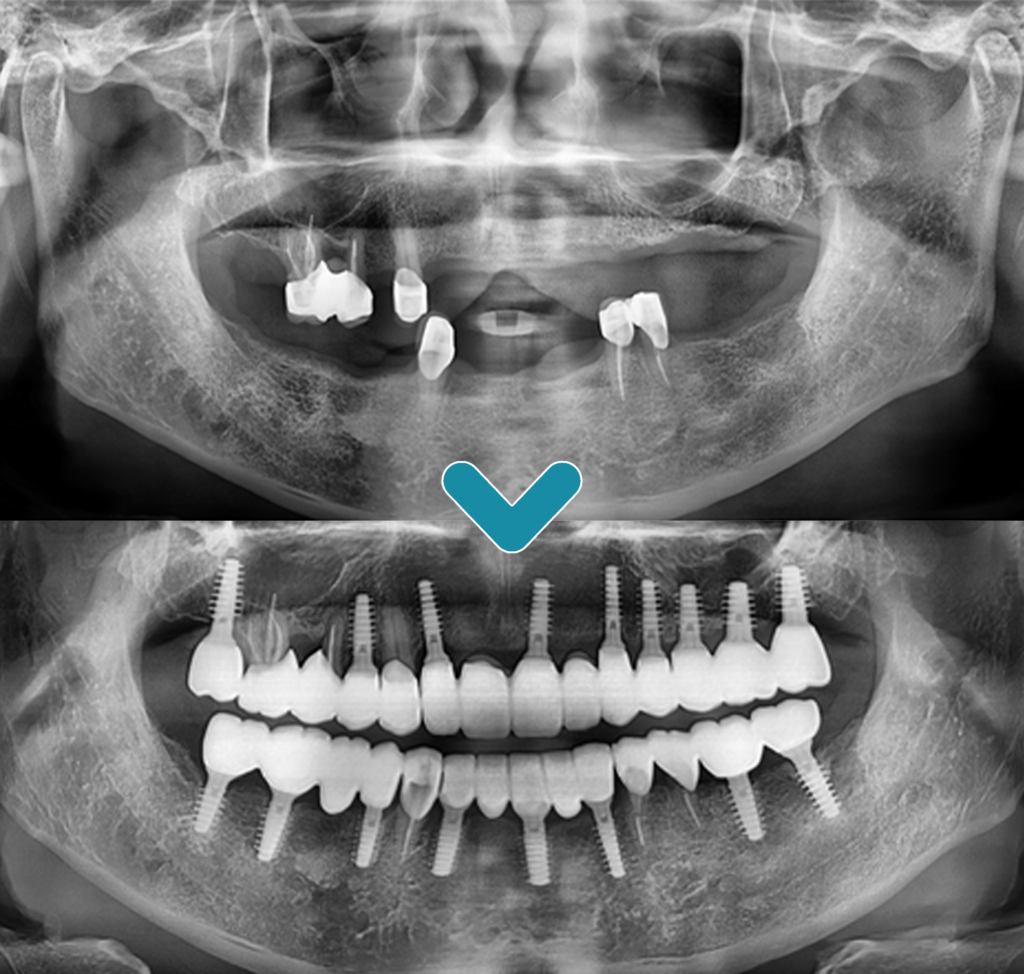

치아가 없는 부위에는 위쪽에 9개,

아래쪽에 8개의 임플란트를 식립하여

전체적으로 이상적인 교합을 맞추며

치료를 완료했습니다.

남아있는 치아 위에 결합된

크라운 보철물은 기존의 부분 틀니에

맞춰 제작된 것입니다.

따라서 위아래의 교합을 정밀하게

맞추기 위해 새로운 보철물을

제작하였습니다.

위 사진은 임플란트 식립 후

5년 후의 정기 검진 시 사진입니다.

프라임치과의 최소침습 임플란트 식립과

더불어 환.자분께서 관리도 잘 해주셔서

건강하게 유지가 잘 되고 있는 모습입니다.

치료 전후의 모습입니다.